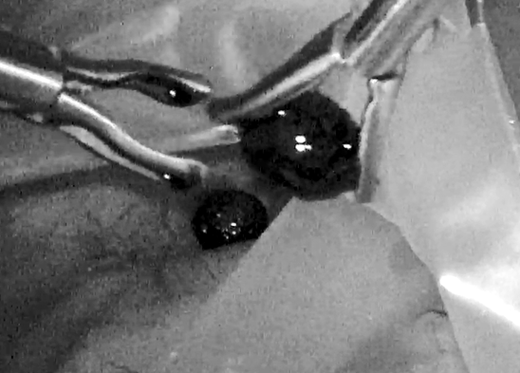

11月30日,湘雅常德医院泌尿外科成功实施首台腹腔镜肾癌根治手术,泌尿外科有了一个良好的开端。 来自桃源县的60岁李爷爷,两个星期前体检发现“右肾肿瘤(肿瘤直径约6cm)”,慕名来到泌尿外科就诊,经泌...